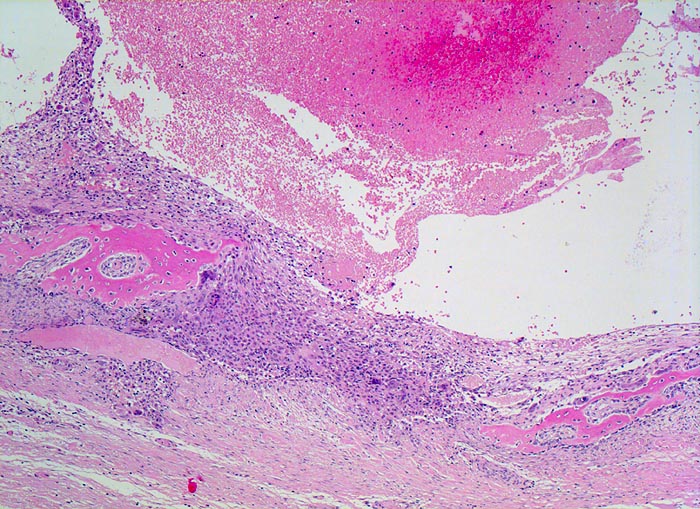

aneurysmatische Knochenzyste (AKZ)

Knochen, Fibula

In der Übersicht erkennt man einen pseudozystischen Hohlraum ohne Epithelauskleidung, welcher Erythrozyten enthält. Pseuozystenwand und $o{as16961Setpum} Septum enthalten Riesenzellen und mononukleäre Zellen. Daneben sieht man parallel zur Pseudozystenwand gelegen neugebildeten Faserknochen, welcher die Wand gleichsam "abstützt".

Lokalisierte Schmerzen und Schwellung in der proximalen Fibula. Im Röntgenbild ist eine Osteolyse erkennbar, die die betroffene Fibula auftreibt. Die Cortikalis über der Osteolyse ist hauchdünn.